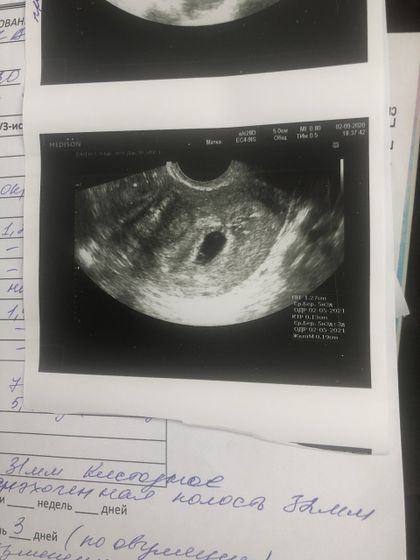

Обратилась в медицинский центр «Импульс», в Кургане. Специалист всё объяснила, показала) Очень довольна приёмом. Единственное НО, образование кистозного тела на правом яичнике. Не напугала, но назначила дюфастон — 4 таблетки сейчас выпить, и лежать. И пропить 20 дней. А вот и моя горошина ? В этот раз, буду осторожней, сохраню маленькую жизнь ♥️

Мне этот срок поставили по овуляции, а не по последней менструации. Если бы по м, то было бы около 7 недель. Вот, как-то так )